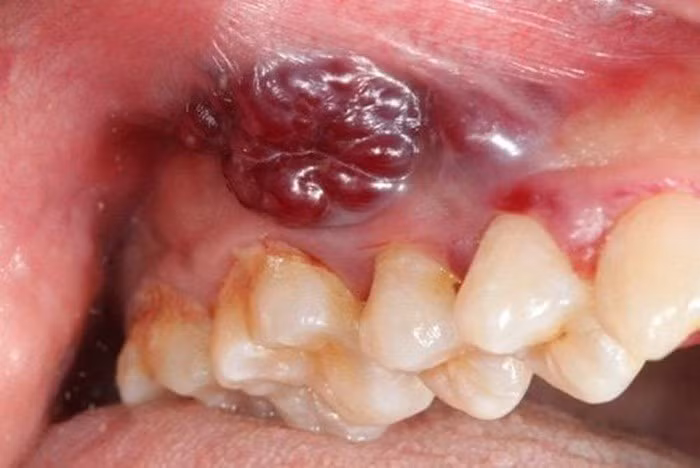

Vùng tổn thương nhô lên kèm loét và chảy máu là dấu hiệu của ung thư khoang miệng/ (Ảnh minh hoạ/Internet)

U nhú màu trắng, thường xuất hiện tại lợi hàm hoặc niêm mạc má và hầu hết không có triệu chứng; Chấm trắng xuất hiện trên nền niêm mạc bình thường với bề mặt gồ ghề và bờ viền không đều; Tổn thương niêm mạc gây ra bởi răng giả hoặc bờ răng sắc nhọn, không lành sau 2 tuần; Tổn thương dạng cục cứng dưới niêm mạc với bờ viền không rõ, không đau và phát triển to ra từ từ.

Niêm mạc trên bề mặt bình thường; Tổn thương niêm mạc không rõ nguyên nhân và không lành sau 2 tuần; Tổn thương không lành sau nhổ răng, sưng đỏ, dễ chảy máu khi chạm vào tổn thương. Một vùng niêm mạc khoang miệng trở nên đỏ và gây đau rát, khó lành; Xuất hiện đau vùng khoang miệng không rõ nguyên nhân, đau ngày càng trầm trọng hơn.